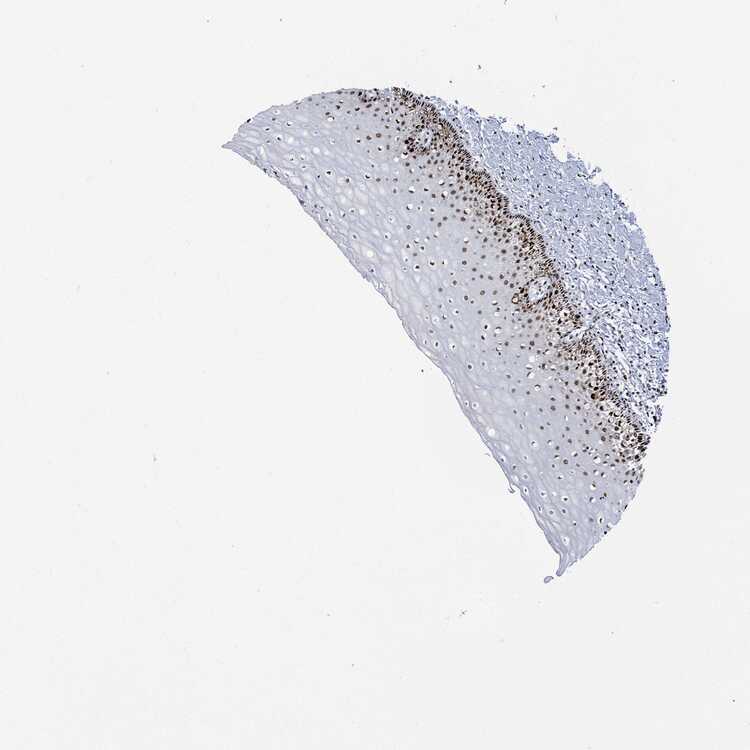

CERVIX - Antibody stainingi

Antibody staining in the annotated cell types in the current human tissue is reported as not detected, low, medium, or high, based on conventional immunohistochemistry profiling in selected tissues. This score is based on the combination of the staining intensity and fraction of stained cells.

Each image is clickable and will lead to virtual microscopy that enables deeper exploration of all samples and also displays staining intensity scores, fraction scores and subcellular localization as well as patient and tissue information for each sample.

Antibody HPA030521Antibody HPA030522Antibody HPA030523Antibody CAB000148Antibody CAB080240Antibody CAB080241Antibody CAB080242

Glandular cells LowHighNot detectedLowNot detectedMediumMedium

Squamous epithelial cells MediumHighMedium-MediumHighHigh